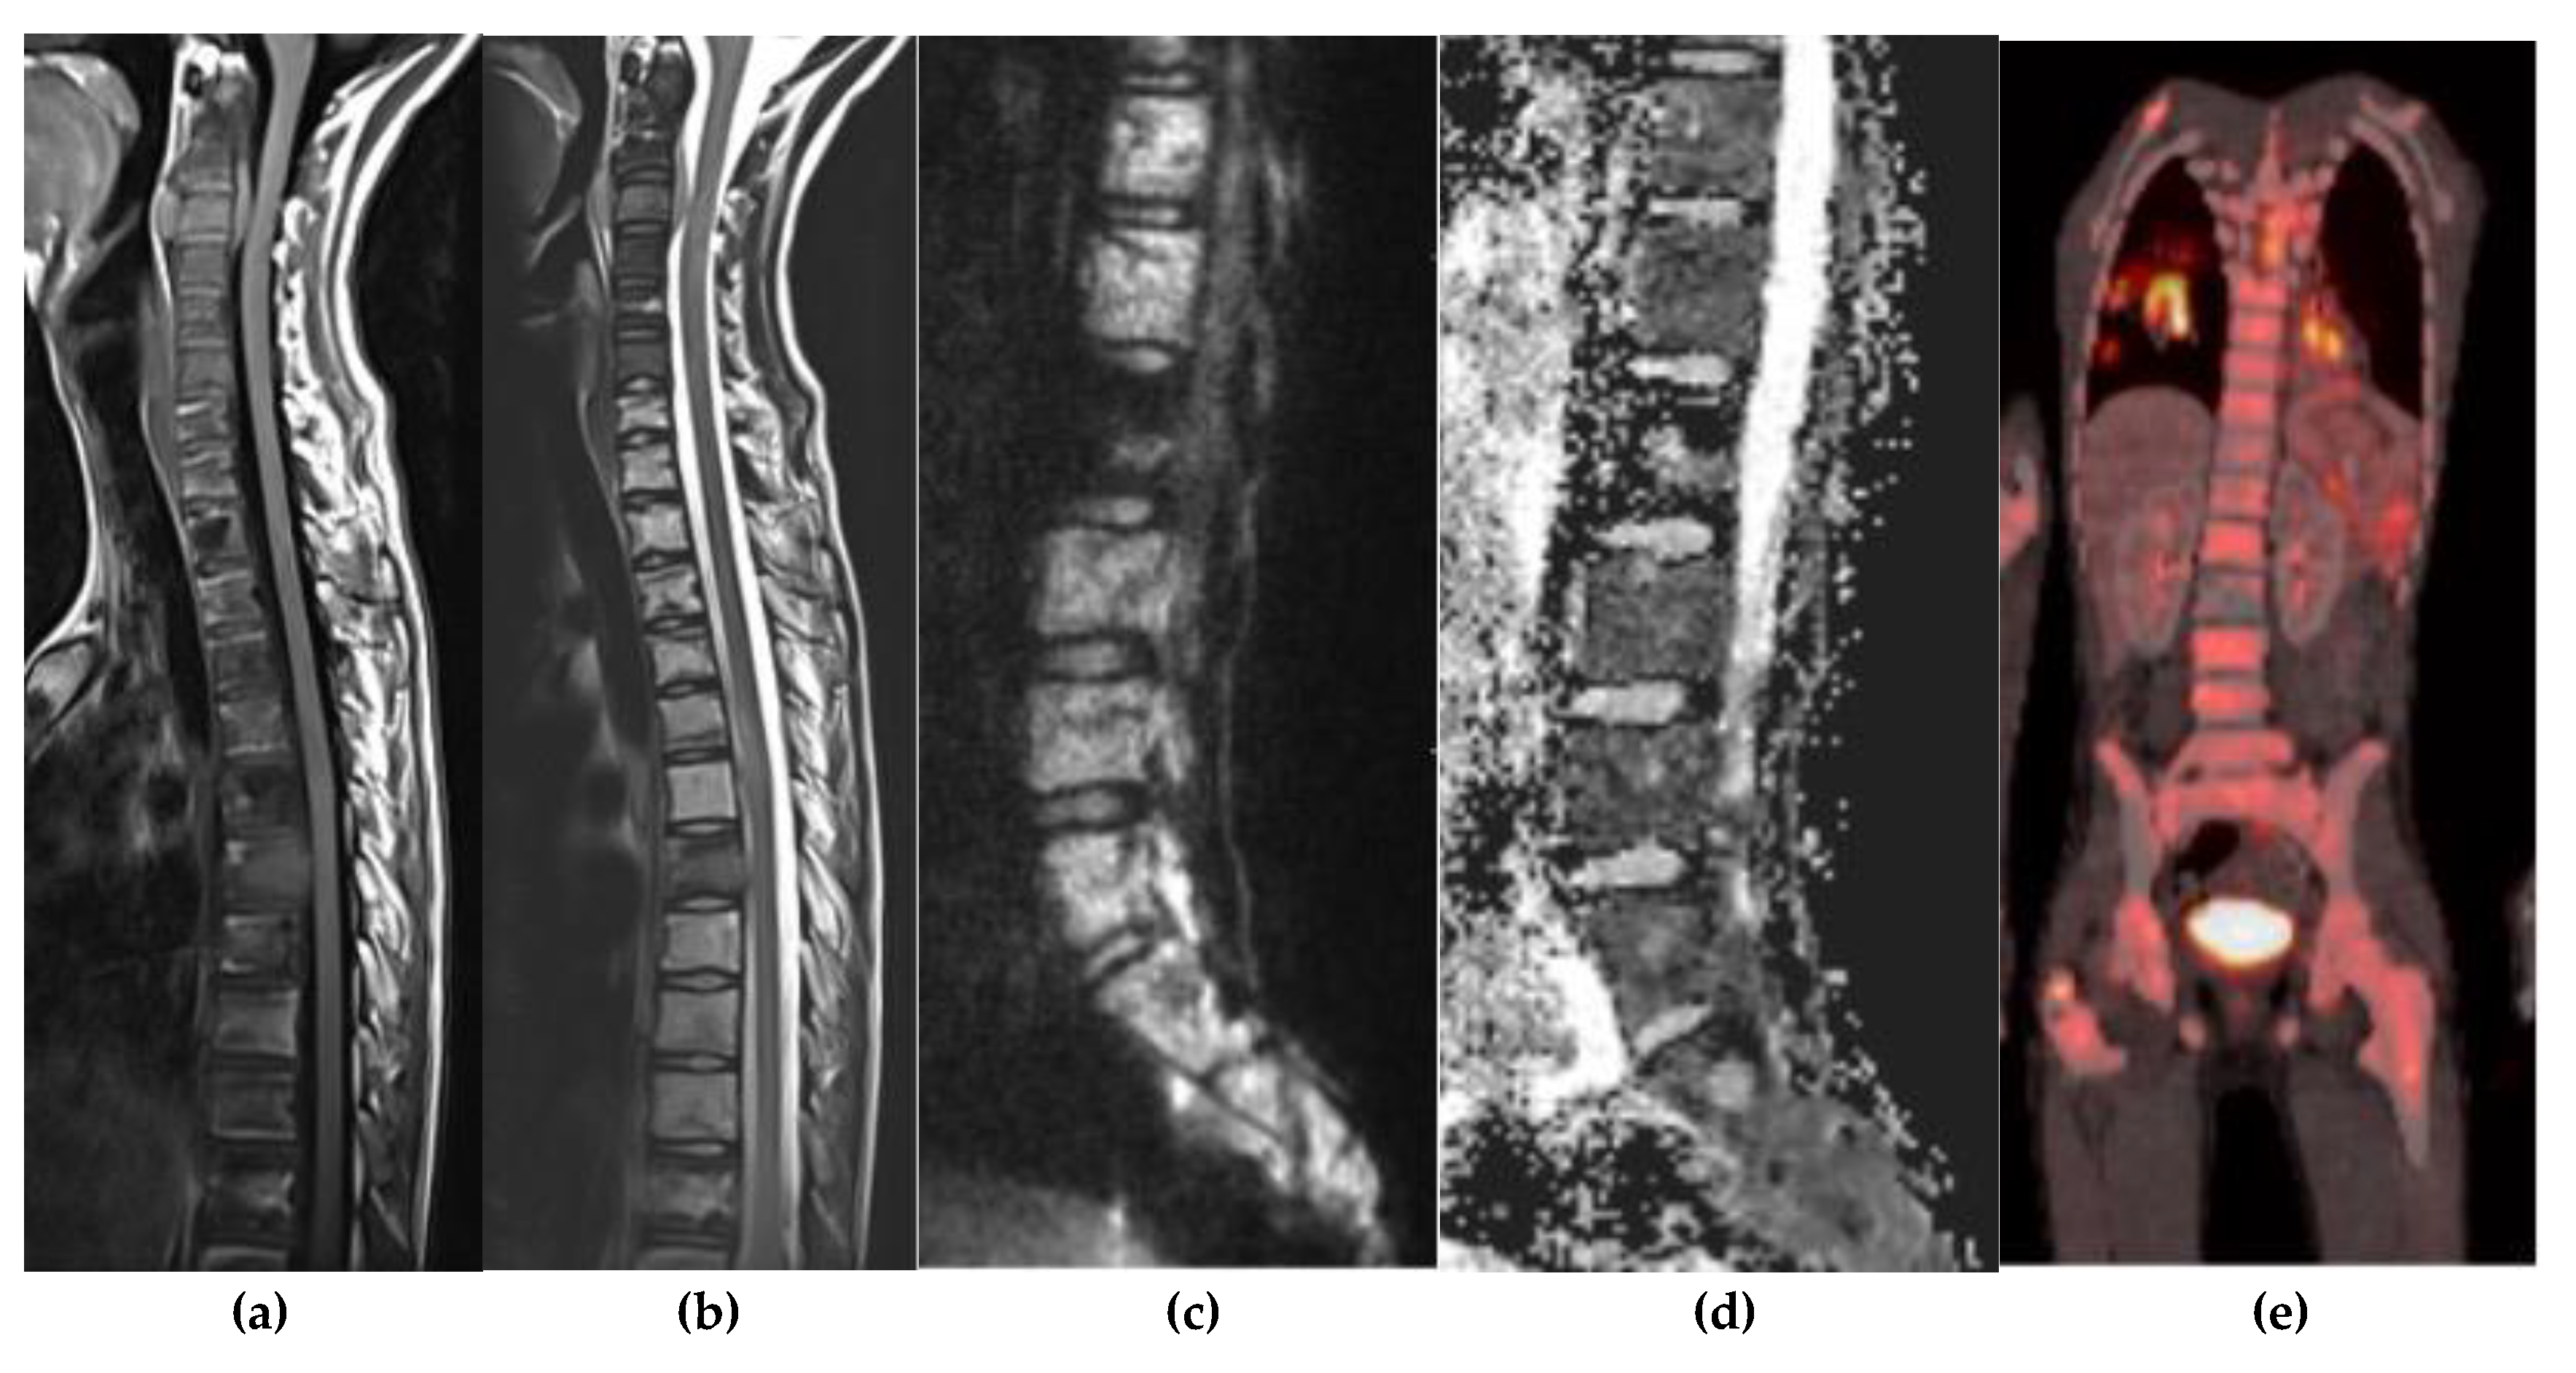

Paget Disease

10. Primitive Small Round Cell

- Dell’Atti, C. , Cassar-Pullicino, V. N., Lalam, R. K., Tins, B. J., & Tyrrell, P. N. M. The Spine in Paget’s Disease. Skeletal Radiol. 2007, 36, 609–626. [Google Scholar] [CrossRef]

- Theodorou, D. J. , Theodorou, S. J., & Kakitsubata, Y. Imaging of Paget Disease of Bone and Its Musculoskeletal Complications: Review. AJR Am. J. Roentgenol. 2011, 196, S64–S75. [Google Scholar] [CrossRef] [PubMed]